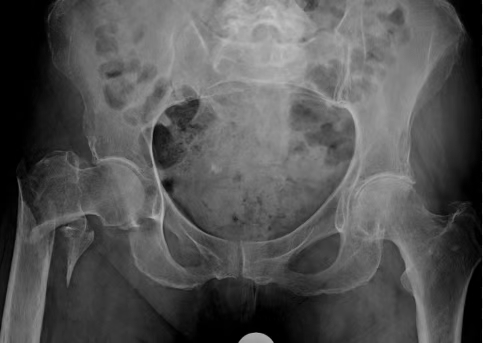

In this study, the authors included 69 patients, of whom 30 were removed suprapatellar and 39 were removed infrapatellar. The suprapatellar group had a higher Lysholm score and a lower VAS score.